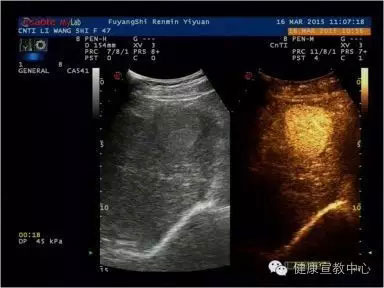

(甲乳分級(jí)診斷彈性評(píng)估技術(shù))

目前,科室開展的聲學(xué)造影已廣泛應(yīng)用到肝臟、膽囊、胰腺、腎臟、脾臟、子宮、甲狀腺、乳腺、淋巴結(jié)等,特別是在乳腺癌診斷尤其是早期病變甚至是癌前期病變的診斷中均取得突破性進(jìn)展。超聲造影、彈性成像及超聲甲、乳結(jié)節(jié)綜合分類法均為2014年在皖北率先相繼開展的新技術(shù),兩年多以來(lái)共開展造影500多例,200多名患者從中受益。隨著我院南區(qū)的全面開診,甲、乳診療中心及其他超聲學(xué)科聯(lián)合體的創(chuàng)立、高端機(jī)器設(shè)備的添置,聲學(xué)造影、彈性成像等新技術(shù)會(huì)拓展到其他學(xué)科,如生殖中心、婦科及外傷性病變等等。

(超聲造影輔助分類)

(肝臟超聲造影)